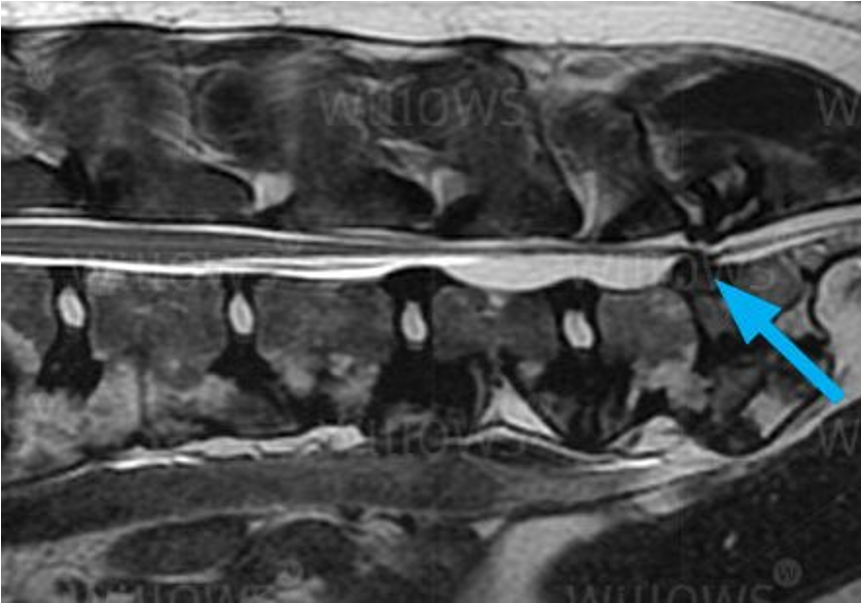

Degenerative lumbosacral stenosis (DLSS) is a leading cause of caudal lumbar pain and cauda equina compression in middle-aged to geriatric large-breed dogs. It involves progressive degeneration of the L7-S1 intervertebral disc, ventral bulging of the ligamentum flavum, foraminal narrowing, and dynamic instability, leading to nerve root compression. Clinical presentation typically includes lumbosacral pain, hindlimb weakness or intermittent lameness, reduced jumping ability, crouched stance, and potential root signature signs.

The 2026 retrospective study by Clemot et al. (Veterinary Surgery) evaluated dynamic MRI in neutral and flexed positions in 24 dogs with confirmed DLSS. Flexion produced significant reductions in intervertebral disc protrusion, protrusion ratios, ventral bulging of the ligamentum flavum, and foraminal compression (p < .001 for all), with complete resolution of cauda equina compression and foraminal occlusion in all cases. Improvement in disc protrusion correlated with the degree of disc degeneration (p = .004). These results suggest that flexion dynamically decompresses affected structures, supporting conservative approaches and questioning routine decompressive surgery when distraction-stabilization is planned.